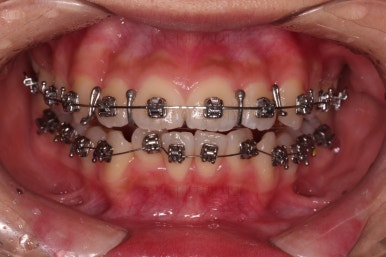

우선 윗니만 장치를 부착했습니다.

순서는 윗니 장치 부착 후 발치를 하고, 가지런하게 된 뒤에, 과개교합 개선을 위한 특별한 장치가 들어가면서 아랫니에도 브라켓을 부착하기로 정했습니다.

이번 환자분이 선택한 장치는 엠파워 메탈이라고 하는 자가결찰 금속 브라켓입니다.

메탈 브라켓이라고 다 구식의 안좋은 장치가 아닙니다.

"자가결찰" 브라켓이면 모두 우수한 성능의 장치인데요.

철사를 잡아주는(결찰) 캡이 브라켓에 달려 있어 스스로 묶을 수 있는(자가) 브라켓입니다.

즉, 세라믹 중에서도 자가결찰인 것이 있고 아닌 것이 있으며, 메탈 중에서도 자가결찰인 것이 있고 아닌 것이 있습니다.

장치를 부착한 직후의 얼굴 모습 변화와 장치가 보이는 느낌을 한 번 봐주시고요.

윗니가 가지런해진 뒤에는 부산치아교정치과 키다리아저씨치과에서는 ABP라고 하는 장치를 사용해 주면서 아랫니에도 브라켓을 부착합니다.

깊게 물리는 과개교합을 개선하기 위함인데요.